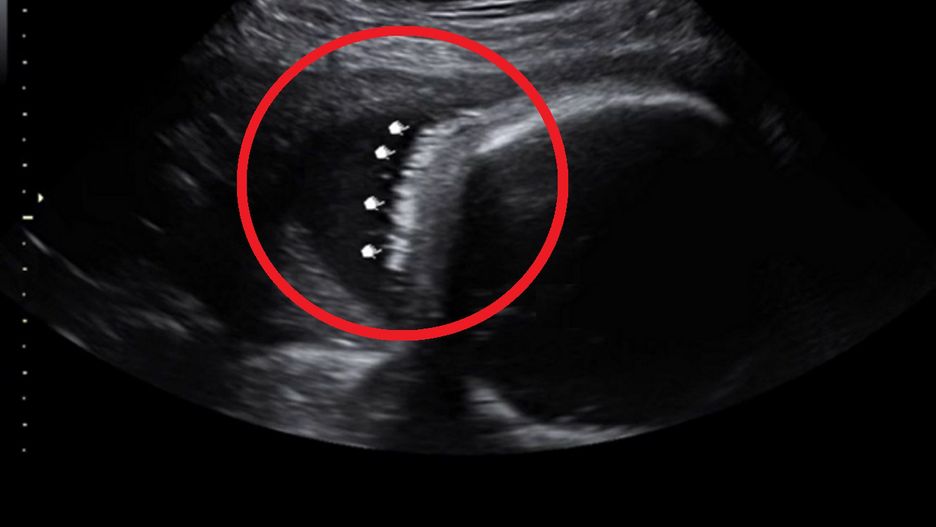

Niektórzy zastanawiają się, czy podczas badania USG można zobaczyć włosy płodu. Okazuje się, że jest to możliwe. Potwierdzeniem jest zdjęcie opublikowane na TikToku przez pewną mamę. Bujne włosy jej dziecka wiązały się także z pewną dolegliwością ciążową.

Badanie USG ciąży pozwala lekarzom przede wszystkim ocenić rozwój płodu i wykryć ewentualne nieprawidłowości. Dzięki obrazom z tzw. USG 3D można również zobaczyć, jak maluszek będzie wyglądał. Zdarza się, że już na tym etapie widać podobieństwo do rodzica bądź... bujne owłosienie.

Tak było w przypadku Jordyn Philips, która już podczas badania usłyszała od specjalisty, że jej córka urodzi się z czupryną. Tak też się stało, co obrazują fotografie prezentowane przez mamę. Widać na nich dziewczynkę z ciemnymi i gęstymi włosami.